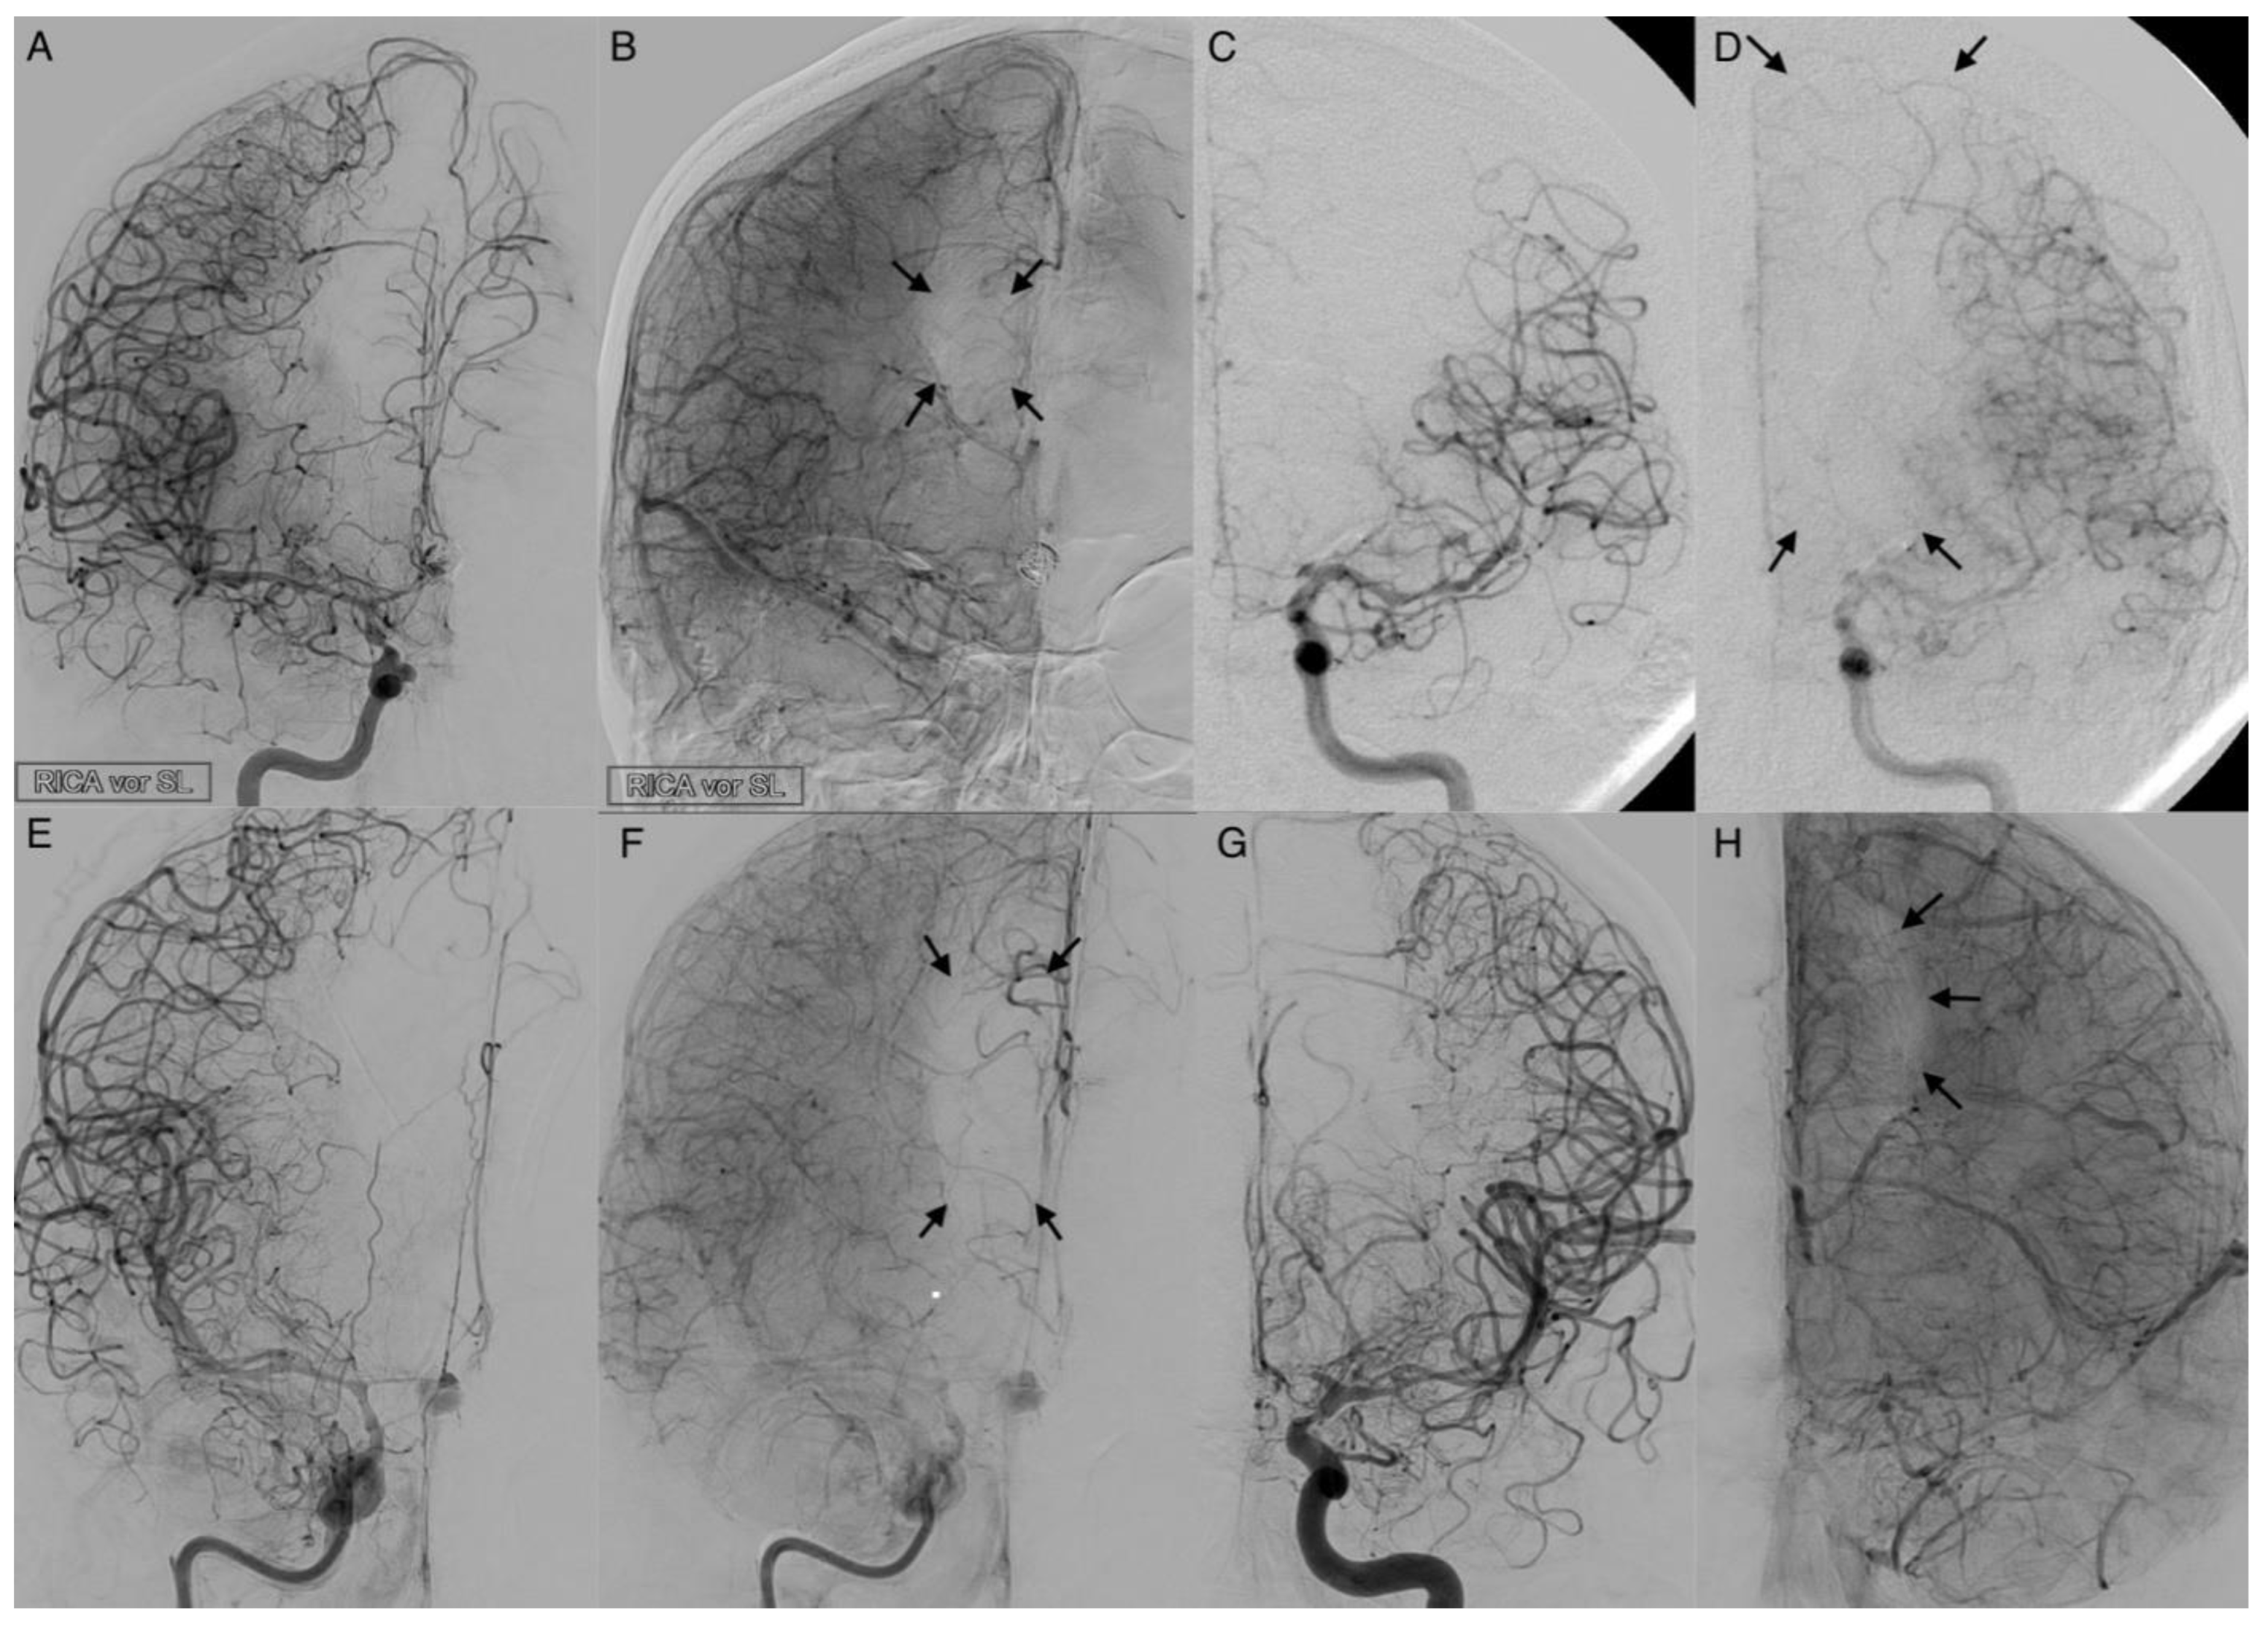

Figure 5. Activated leptomeningeal collaterals in anterior cerebral artery vasospasm. The angiograms show the extent of collateralization in four cases of severe cerebral vasospasm following aneurysmal subarachnoid hemorrhage. The arterial phase (A,C,E,G) reveals a strongly narrowed and decelerated anterior cerebral artery. In the parenchymal phase (B,D,F,H), activated leptomeningeal collaterals of the middle cerebral artery took over the retrograde supply of the decelerated parenchyma with varying extent of the remaining perfusion defect (arrows).

3.4. Leptomeningeal Collaterals

The activation of leptomeningeal collaterals between the MCA and ACA territory was assessed in p.a. projection. The varying ability of collateral supply is shown in Figure 5 and Figure 6. Two patients first had activated collateral supply, but later had collapsed collateral supply (Figure 6). The distinct outcomes with mRS values of 3 and 5, despite subtotal hemispheric infarction, were caused by the laterality of language ability.

In all cases with collateral supply, vasospasm had affected the ACA hardest, requiring leptomeningeal collaterals to take over the anterior and border zone supply. Only 37.2% (n = 16) of patients revealed a leptomeningeal collateral activation on angiograms (Table 1). Fourteen patients (87.5%) with leptomeningeal collateral activation showed a positive STA sign on angiograms with a positive correlation in Pearson’s correlation (Correlation coefficient: 0.318, p = 0.038). Overall, Fisher’s test indicated no significance for the prediction of outcome (p = 1) or DCI (p = 0.719) in the context of leptomeningeal activation.

Only 32.7% of the patients in our study developed angiographically visible leptomeningeal collaterals for ACA territory supply. However, in our analysis, these collaterals had no significant predictive value for patients’ outcome or DCI-related infarctions. In accordance with the literature [16], patients with fewer or collapsed leptomeningeal collateral vessels had worse outcomes, excluding other severe complications. Subtotal hemispheric infarctions closely followed collapsed collaterals.